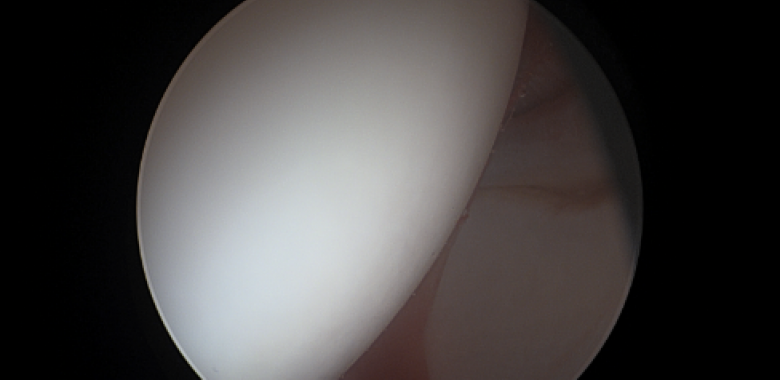

Η ακρίβεια στην οστεοπλαστική στη μορφολογία cam, αποτελεί ένα φλέγον ζήτημα τα τελευταία χρόνια.  Έχουν προταθεί διάφοροι τρόποι για ακριβή αφαίρεση οστού κατά τη διαδικασία αυτή, και υπάρχουν νέες τεχνολογικές και πολλά υποσχόμενες τεχνικές που εφαρμόζονται σε πολλά κέντρα. Ένας προτεινόμενος τρόπος για αυξημένη ακρίβεια είναι το Computer Navigation, το οποίο χρησιμοποιείται σε πολλά κέντρα του εξωτερικού.

Σε μία νέα μελέτη έγινε προσπάθεια να εκτιμηθούν τα αποτελέσματα της χρήσης ενός συστήματος Computer Navigation σε ασθενείς με μορφολογία cam ή συνδυασμό μορφολογίας cam και pincer, και να συγκριθούν τα αποτελέσματα με τεχνική free hand (τεχνική χωρίς ηλεκτρονική βοήθεια).

Η μελέτη αυτή ήταν αναδρομική και συμπεριλάμβανε ασθενείς που αντιμετωπίστηκαν μεταξύ των ετών 2020 και 2014, και υπεβλήθησαν σε πρωτοπαθή αρθροσκόπηση ισχίου για cam ή μικτή μορφολογία.  Eίχαν διαθέσιμη προεγχειρητική και μετεγχειρητική αξονική τομογραφία του ισχίου και είχαν ελάχιστη παρακολούθηση 12 ετών.  Χωρίστηκαν σε δύο κατηγορίες και η μία υποβλήθηκε σε χρήση συστήματος Computer Navigation, ενώ η δεύτερη σε συμβατική, χωρίς βοήθημα τεχνική. Η εκτίμηση του προχειρητικού πλάνου εκτιμήθηκε με τη διενέργεια μετεγχειρητικής τρισδιάστατης αξονικής τομογραφίας σε κάμψη 90°, 70° και 45°.  Για την εκτίμηση του κλινικού αποτελέσματος χρησιμοποιήθηκαν οι κλίμακες αξιολόγησης Harris Hip Score και Non-Arthritic Hip Score.

Συνολικά συμπεριελήφθησαν 55 ισχία (25 στην ομάδα της navigation και 30 στη συμβατική τεχνική).  Ο μέσος χρόνος παρακολούθησης ήταν 14,7 ± 4,4 μήνες στην ομάδα navigation και 31,3 ± 11,2 μήνες στην ομάδα της συμβατικής τεχνικής.  Στον ένα χρόνο το Non-Arthritic Hip Score είχε στατιστικά σημαντική διαφορά στην ομάδα του navigation, όμως η κλίμακα αξιολόγησης Harris Hip Score, το ποσοστό επανεγχείρησης και μετατροπής σε ολική αρθροπλαστική ισχίου ήταν το ίδιο και για τις δύο ομάδες.

Οι συγγραφείς συμπέραναν ότι το computer navigation μπορεί να βελτιώσει την ακρίβεια στην αφαίρεση οστού και να οδηγήσει σε καλύτερα μεσοπρόθεσμα αποτελέσματα όσον αφορά το Non-Arthritic Hip Score, ωστόσο τα πλεονεκτήματά του είναι περιορισμένα όσον αφορά τα αποτελέσματα του Harris Hip Score, το ποσοστό επανάληψης της αρθροσκόπησης και μετατροπής σε ολική αρθροπλαστική ισχίου.